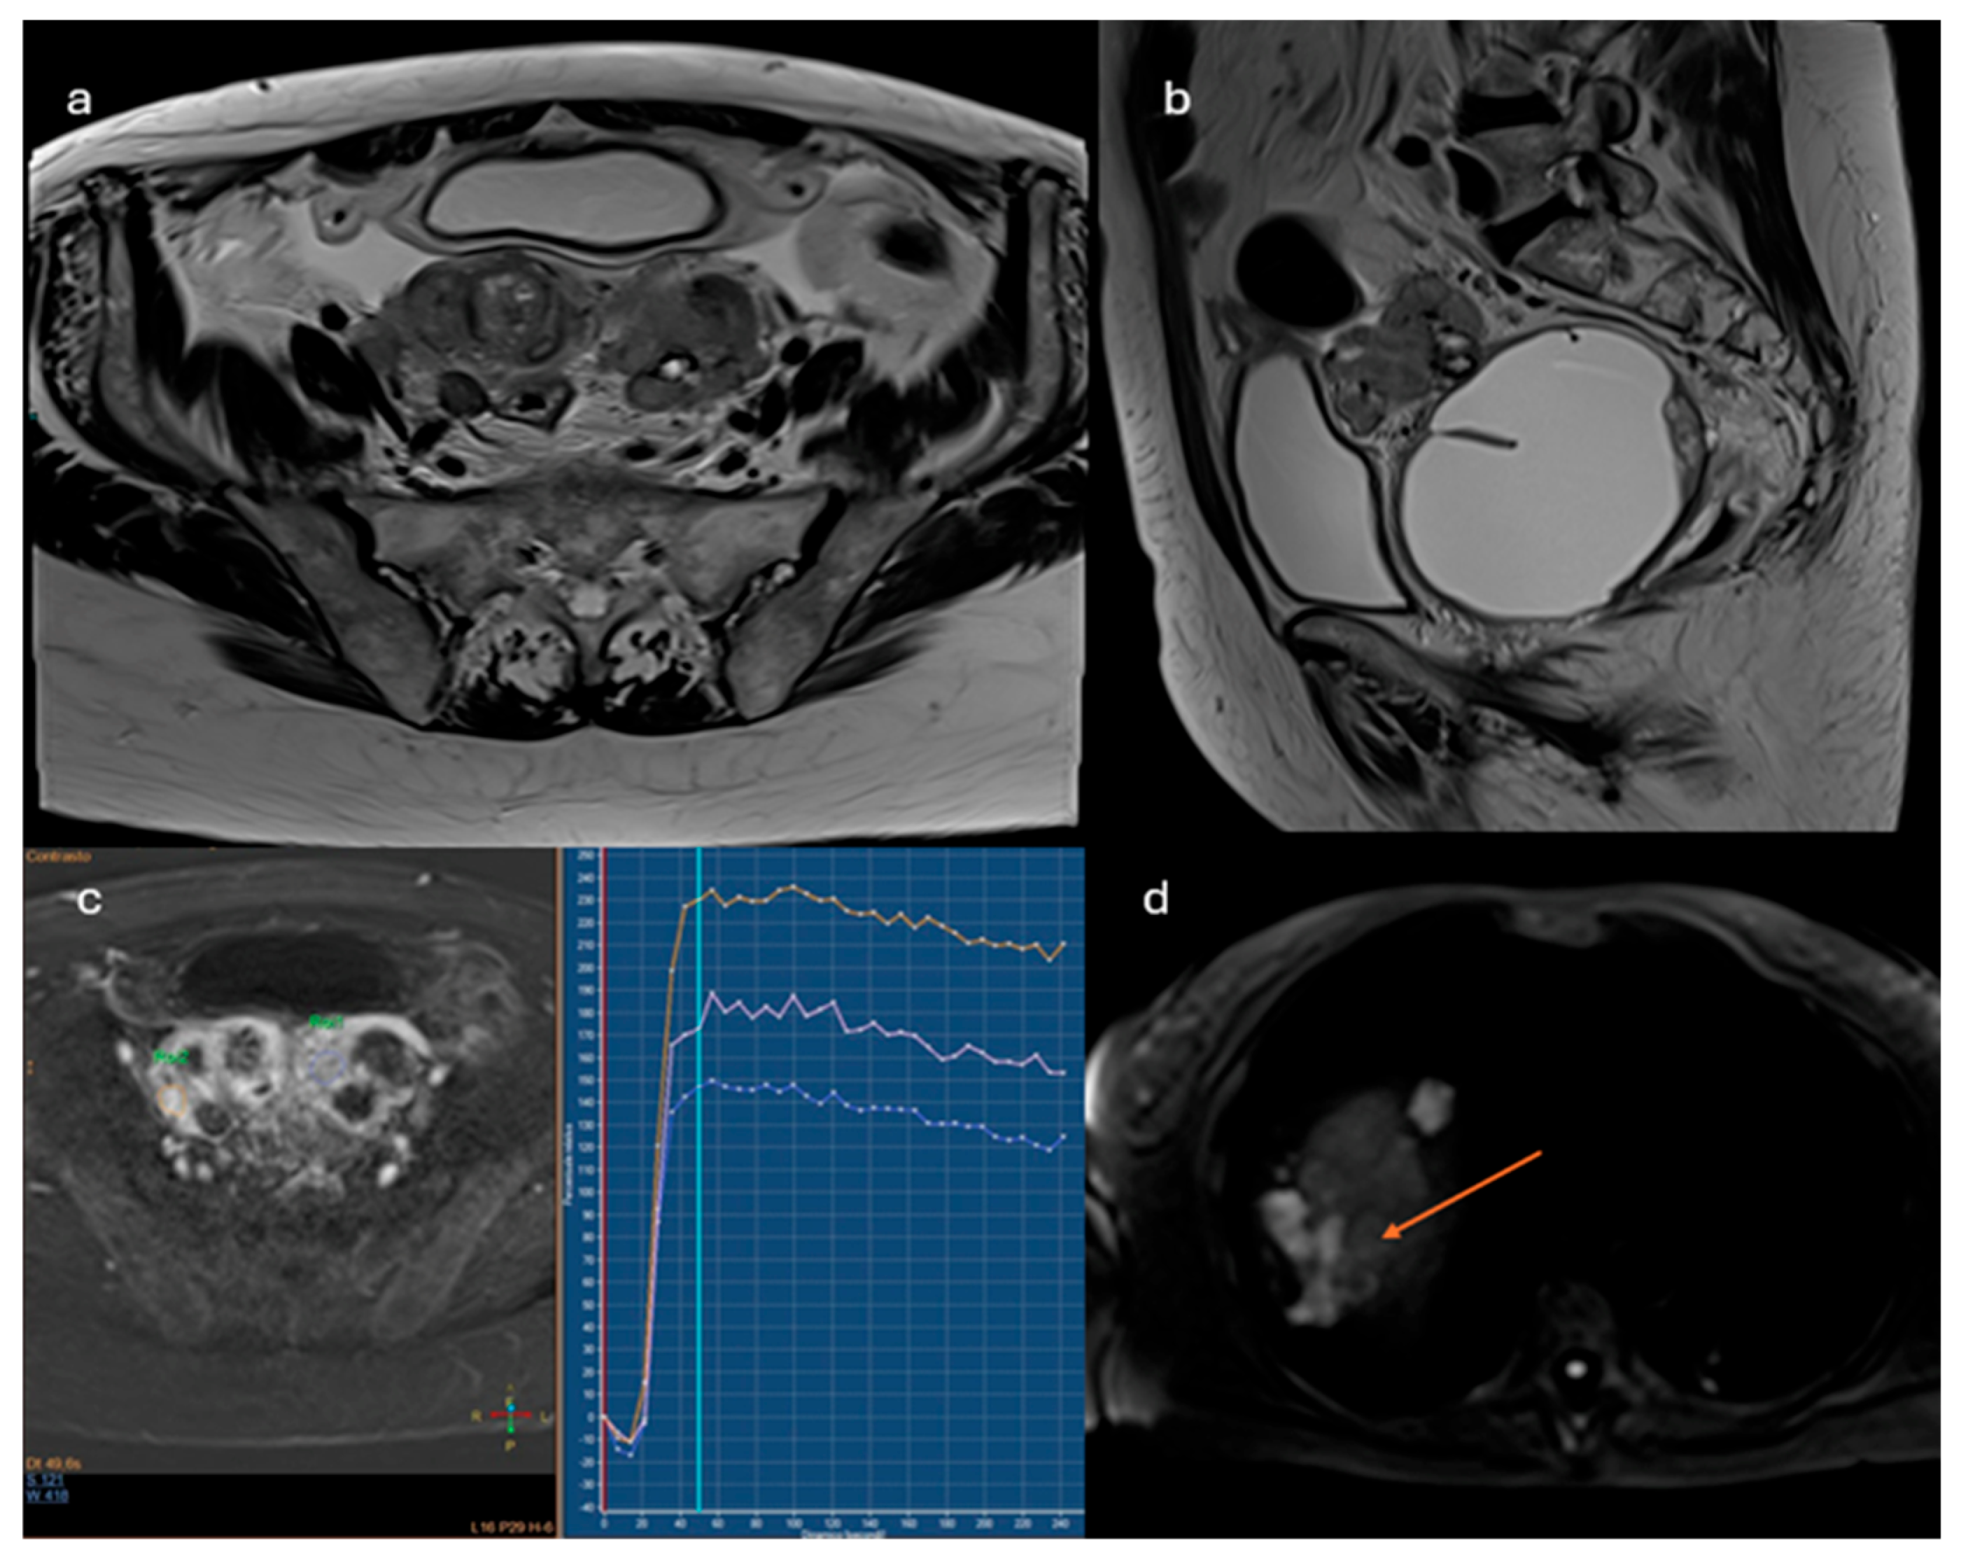

2.3.2. O-RADS MRI Score

- Lesions showing a type 3 enhancement curve (high risk)

- Solid lesions showing enhancement > myometrium at 30-40 seconds, if perfusion study is not available

- Lesions associated with the presence of peritoneal implants and/or secondary disease localization (Figure 5)